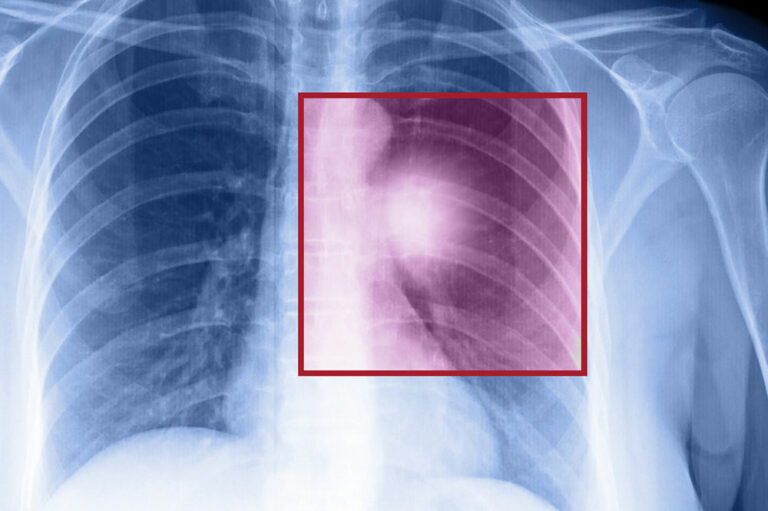

Lung cancer is among the most common causes of cancer-related deaths in our country. While smoking and an unhealthy lifestyle are the major risk factors associated with lung cancer, the disease can also result from breathing poor quality air. Places with a lot of air pollution are therefore known to report more lung cancer cases. In this article, we have listed five cities that have the highest rates of lung cancer.